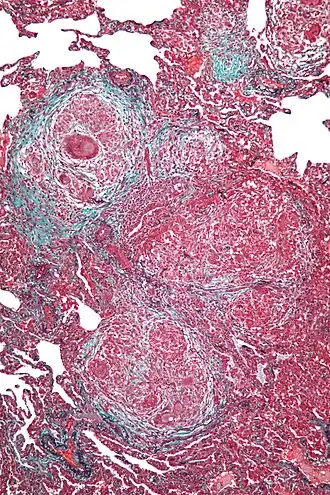

В конце XIX века Роберт Кох впервые наблюдал гиперчувствительность замедленного типа при введении туберкулёзных бацилл в кожу зараженного туберкулёзом животного. Такая инъекция через 1-2 суток вызывала местное воспаление с образованием гранул. В свою очередь, у здоровых животных реакция была слабой и кратковременной.